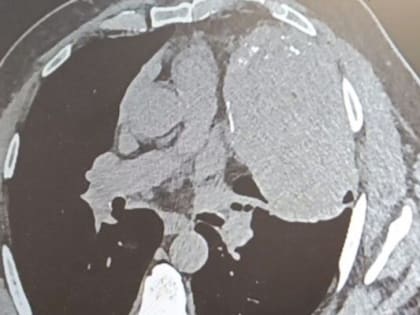

Снимок внутренних органов. Источник: Минздрав Оренбургской области В Оренбурге врачи удалили огромное новообразование в грудной клетке у жителя Орска, которое начало формироваться между сердцем,

В Оренбурге хирурги удалили огромную опухоль из груди пациента

Торакальные хирурги Оренбургской областной клинической больницы №2 провели сложную операцию и удалили у жителя Орска огромное новообразование в грудной клетке.